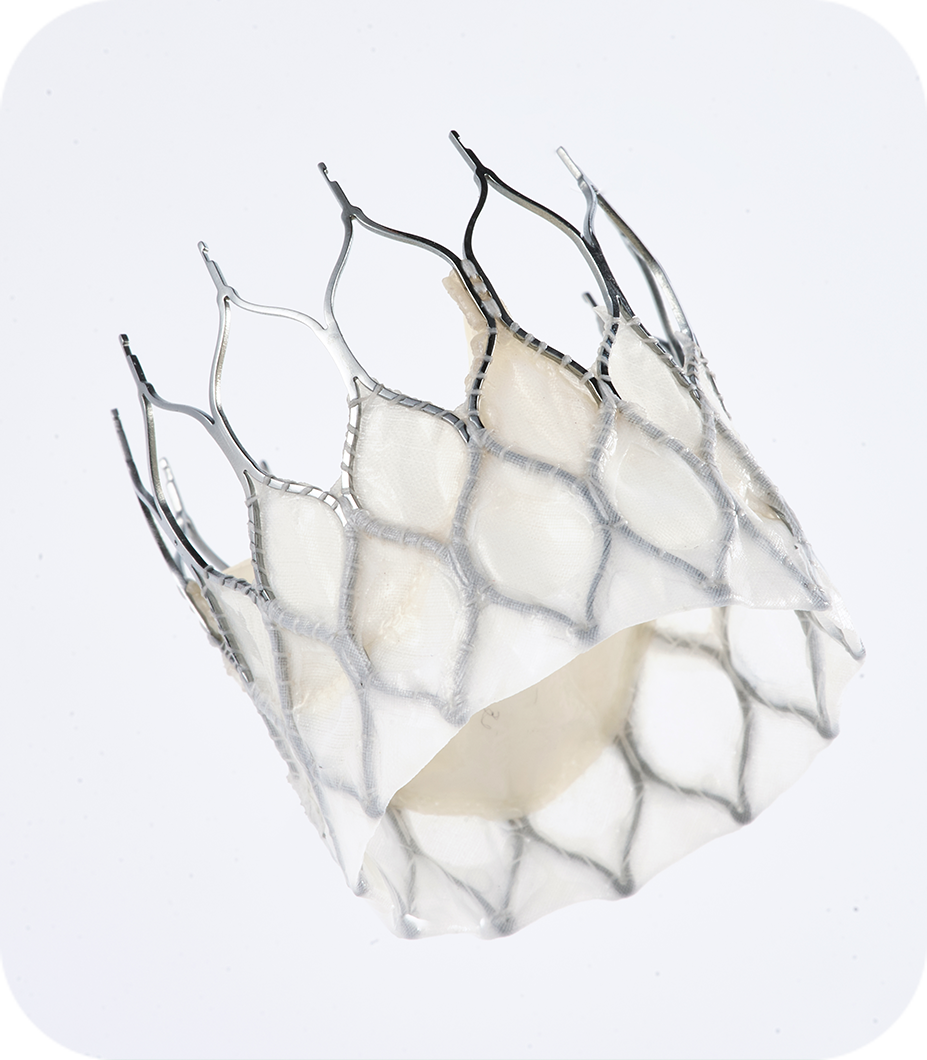

✅预弯型设计:装载后瓣膜与系统成角度挂载,配合短瓣架柔性连接设计,自动适应主动脉弓弯形,轻松通过小弓角等挑战弓部,同时能够自动调整跨瓣角度,减少辅助器械和补救器械的使用。(第一例72°横位心,第二例67°锐角弓,均未使用snare辅助)。

✅以上两例患者均为高钙化二叶瓣患者,最终均获得较好的血流动力学表现。ScienCrown全瓣架参与支撑,提供充足的径向支撑力,同时可兼顾顺应性,刚柔并济,完美适配高钙化与二叶瓣患者特征,临床试验二叶瓣患者比例高达63.28%,重度钙化比例高达54.69%,一年随访有效瓣口面积1.88cm2。

该批手术的成功再次印证了我国结构性心脏病TAVR领域的突破性进展,其核心在于技术路径的精准把控与创新器械的协同应用。作为国产高端医疗器械的创新代表之一,乐普心泰ScienCrown瓣膜采用创新短支架自膨胀设计,融合了“自膨瓣”与“球扩瓣”的双重优势。其输送系统的预弯型设计显著提升了瓣膜的通过性与植入的同轴性,与常规自膨胀瓣膜仅能部分释放不同,该款瓣膜支持100%完全释放,便于术者直观评估瓣膜形态及其对冠脉的影响,有效规避了传统自膨胀瓣膜因同轴性不足带来的二次位移风险,达成了瓣膜位置的可控调节。这一创新TAVR系统,不仅实现了国产瓣膜锚定、瓣膜释放及临床效果等方面的进化发展,更为复杂解剖结构患者提供了兼具安全性与操作确定性的治疗新方案。